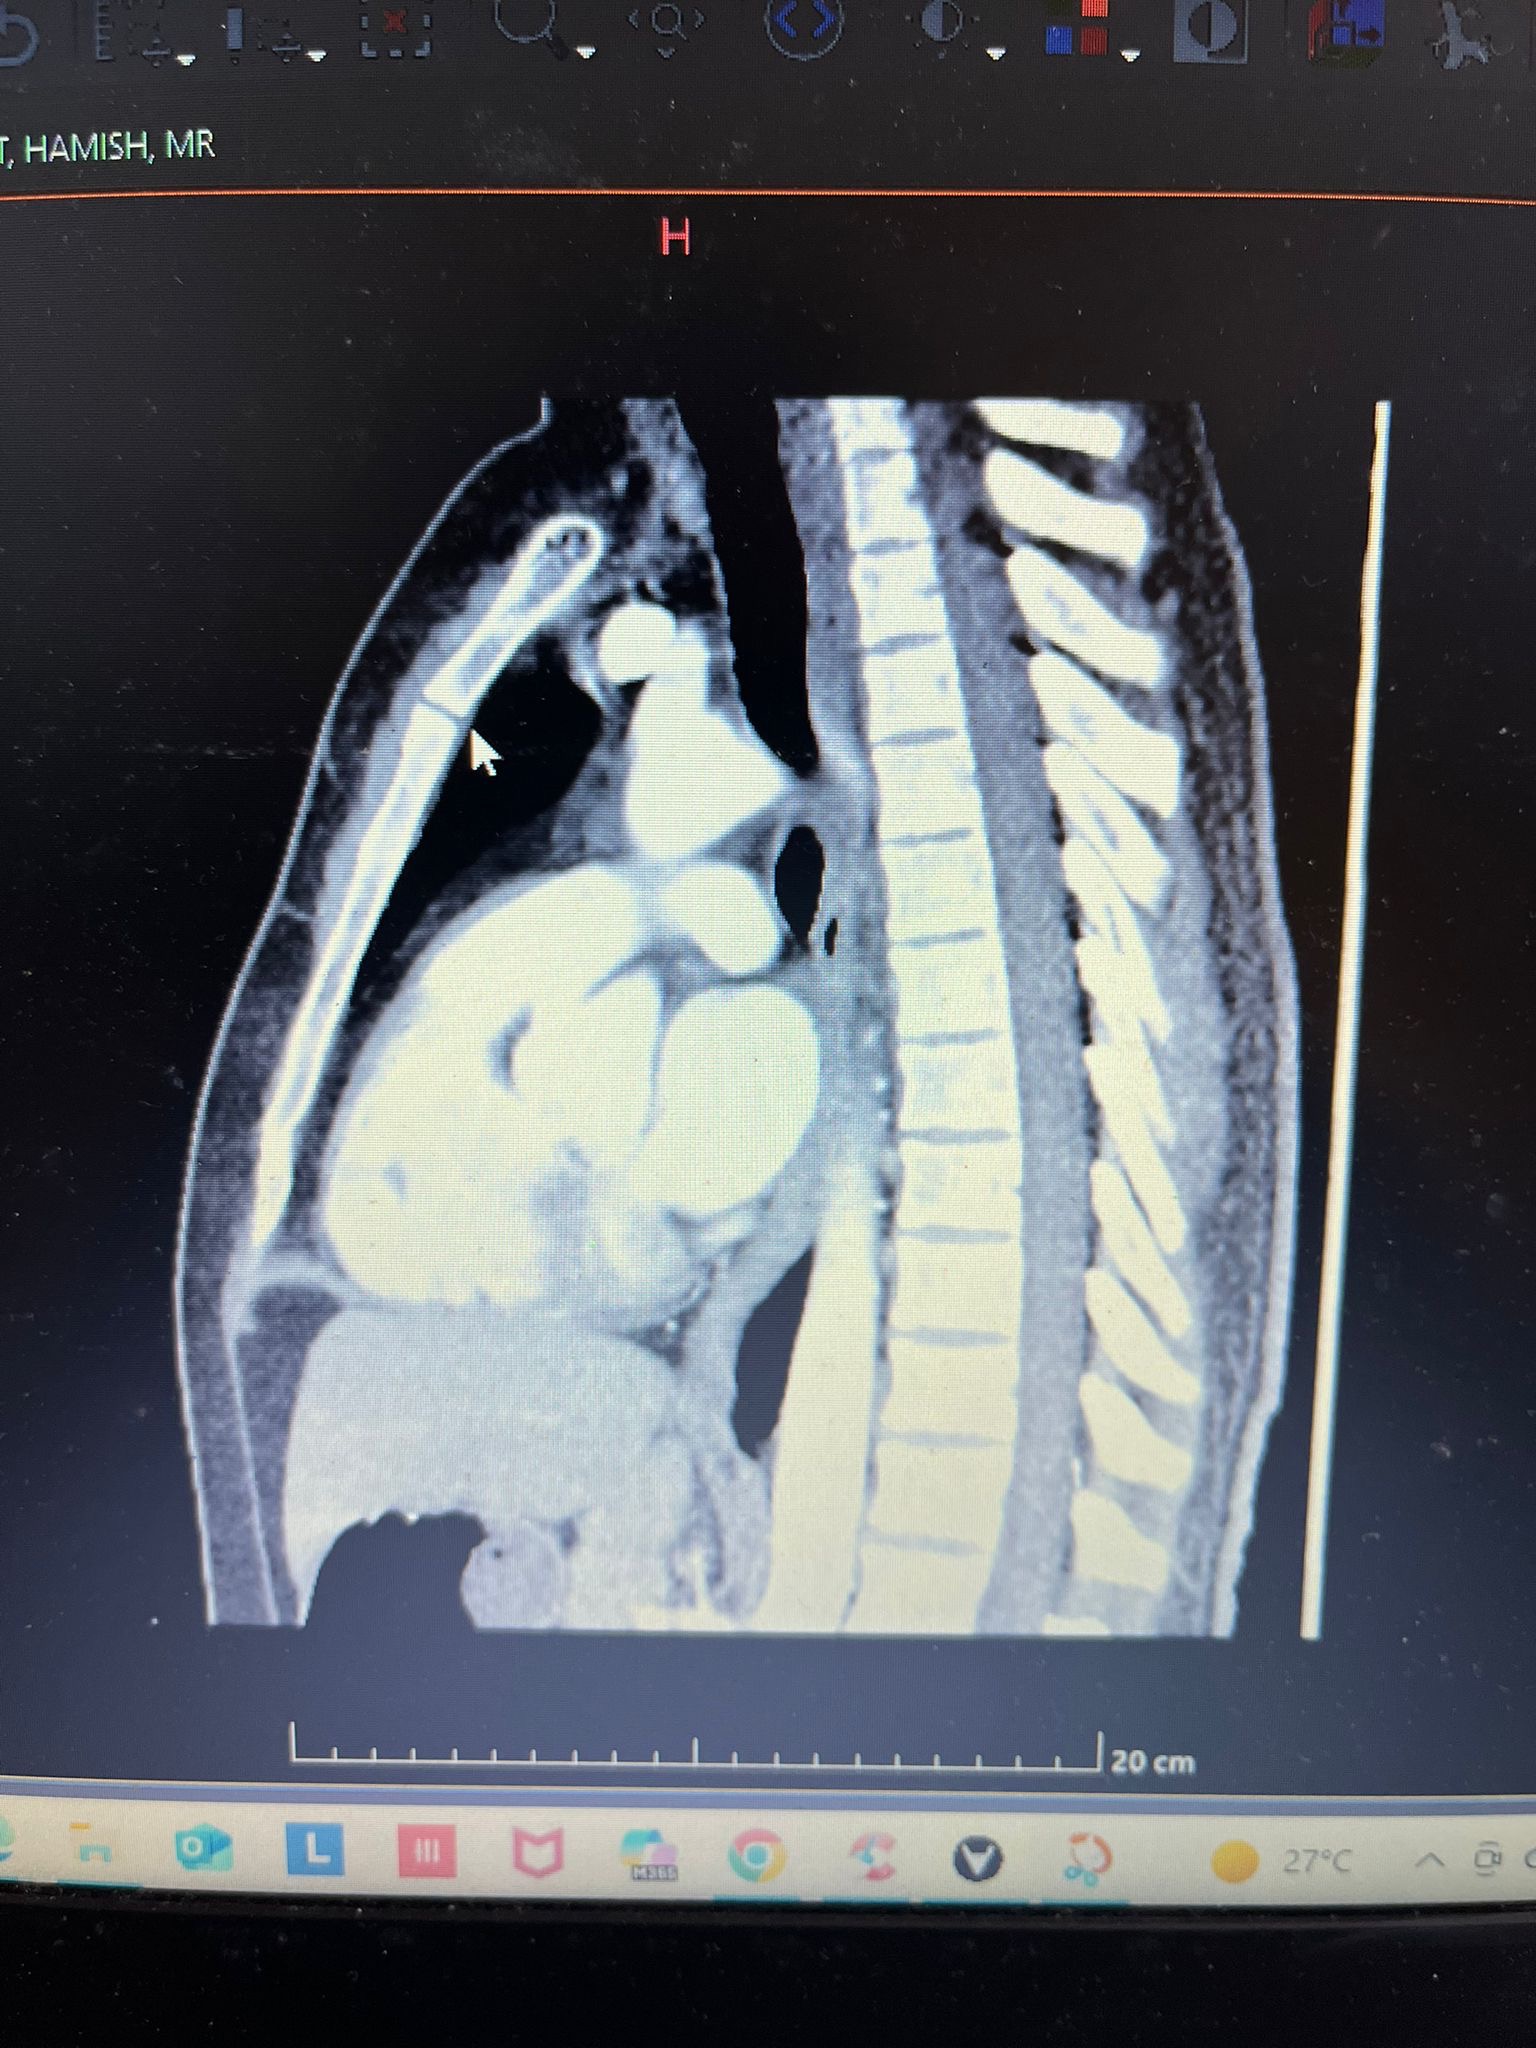

The accident left him with a fractured sternum and the loss of eight front teeth, possibly more. He’s now facing months, possibly years, of dental work. It’s a lot to take in, and it’s going to be a long road.